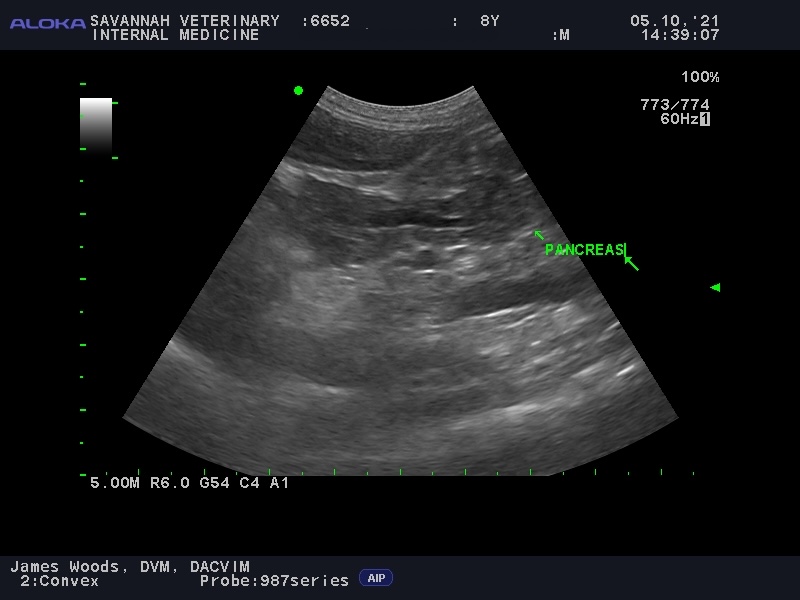

Visualizing The Pancreas: For the diagnosis of feline pancreatitis, an abdominal ultrasound is an important diagnostic tool. While X-rays are typically not very useful, ultrasound provides a non-invasive way to visualize the pancreas. The accuracy of ultrasound is highly dependent on the skill of the operator, as the pancreas can be difficult to locate and assess in cats. At Savannah Veterinary Internal Medicine, our team performs detailed ultrasounds to help identify pancreatitis, even in subtle cases. Even more so than the fPLI test, ultrasound may be normal in cats with mild, or chronic pancreatitis.

To illustrate this diagnostic challenge, the appearance of the pancreas on ultrasound varies significantly between different forms of the disease:

Acute vs. Chronic Feline Pancreatitis Ultrasound Images:

Recognize the varied imaging features of the inflamed feline pancreas, where acute and chronic forms present with distinct ultrasonographic changes.